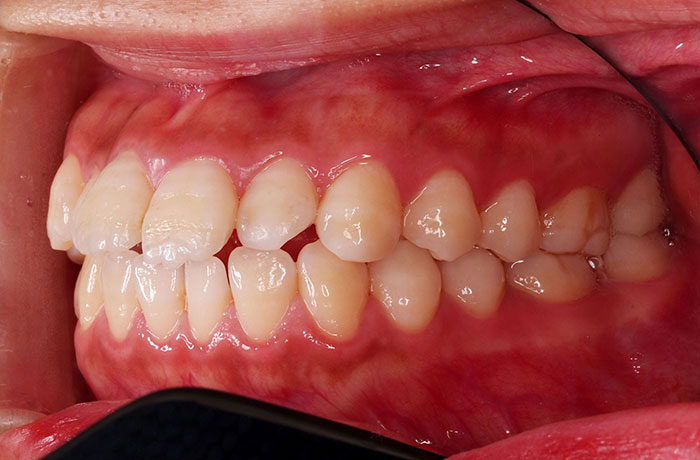

after

年齢 27歳

性別 女性

治療名称 マウスピース型カスタムメイド矯正歯科装置(インビザライン)・コンプリヘンシブパッケージ(フルパッケージ)

総額治療費用 770,000円(税込10%) 金額備考 精密検査料・診断料 33,000円(税込10%)

治療期間 1年11か月 通院頻度など 40日ごと

1枚につき10日装着を指示しました。

患者の症状 上顎前歯の前突、八重歯

治療方法 上下左右の第一小臼歯抜歯で、マウスピース型カスタムメイド矯正歯科装置による矯正

治療結果 上顎前歯の前突、八重歯が改善されました。

歯並びをより良くするために追加でアライナーを発注しました。

リスク/副作用 決められた時間装着する必要があります。